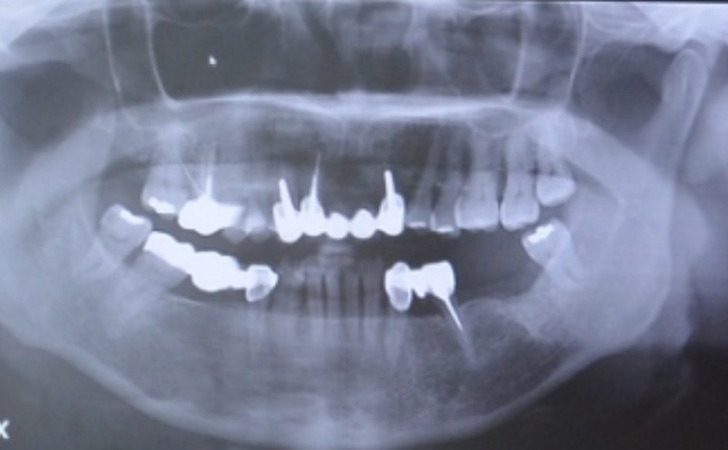

她自己反而沒有一口好牙

早期年代醫療沒有那麼發達

蛀牙治療方式就是牙齒蛀很深醫師就會建議拔掉

所以媽媽才近六十歲口腔裡面就有一半都是牙橋跟缺牙來支撐

時代的差距造就口腔健康與否